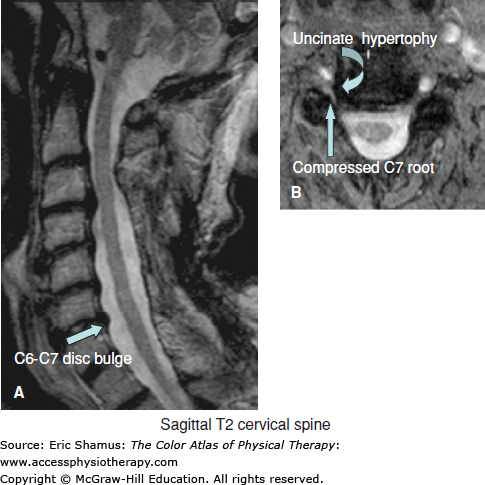

Scenario: A 57-year-old male presents with reports of left-sided neck, shoulder, and arm pain persisting for the past eight months. He does not recall a specific injury and reports a gradual onset of pain. Symptoms are described as aching with burning and numbness into the arm and hand. He works as a medical billing specialist and reports increased symptoms after sitting at his desk for over an hour and driving his car for extended periods of time. Cervical left side bending and rotation movements increase arm pain and manual distraction provides symptom relief. Significant forward-head posture is noted along with weakness of the bilateral rhomboids, middle trapezius and serratus anterior. Diminished sensation is noted over the left thumb along with weakness of the left wrist extensors.